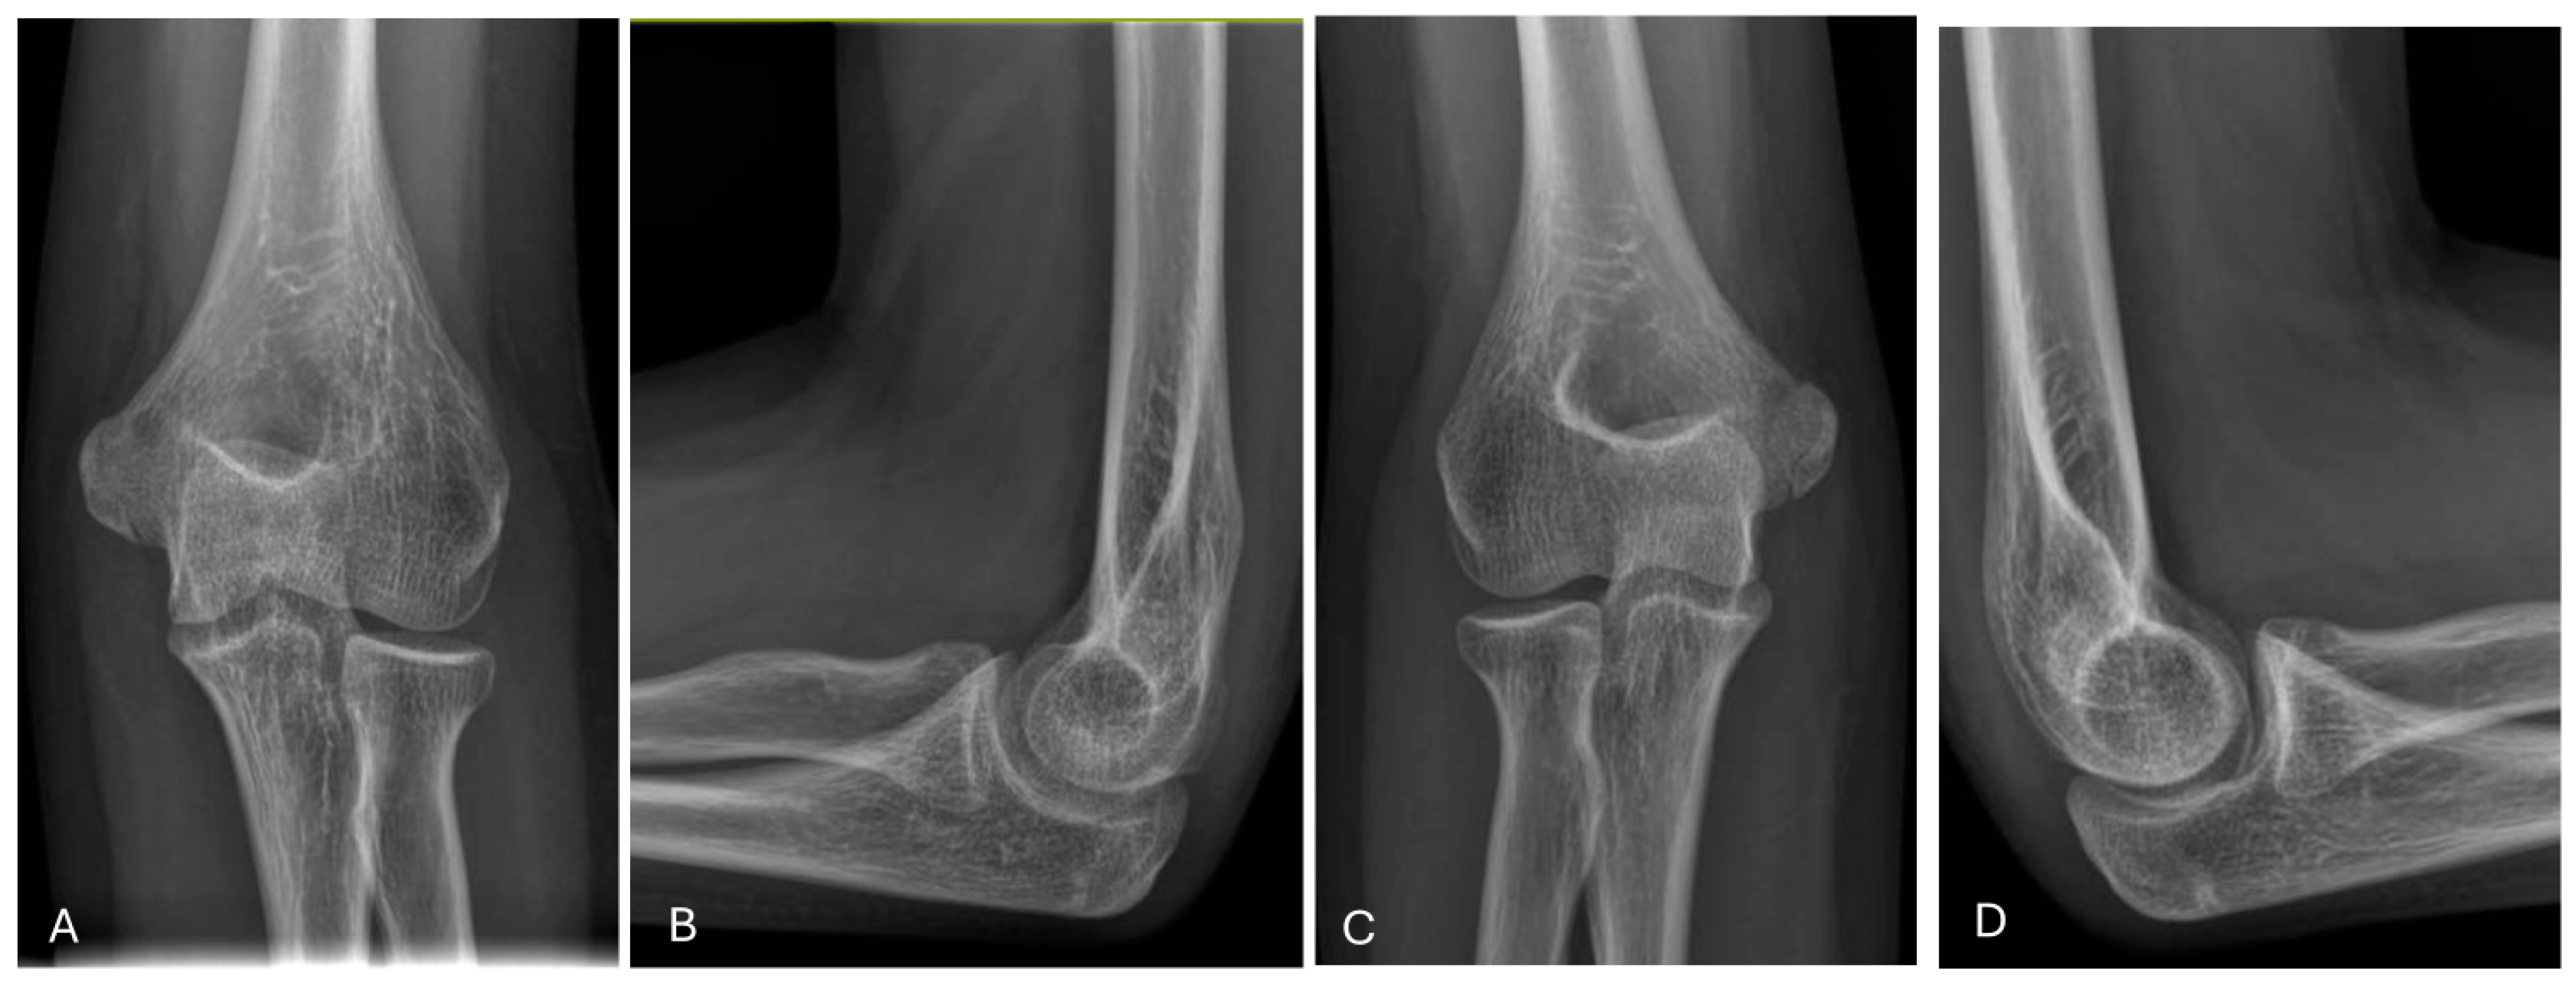

Lateral Humeral Condyle Fracture in Childhood: Results of a New Surgical Technique

1. Introduction

2. Materials and Methods

3. Results